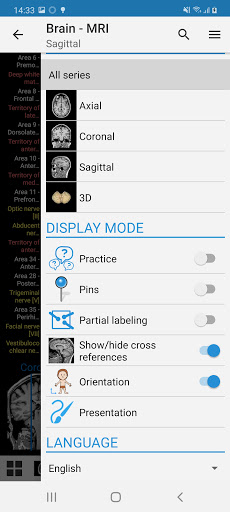

e-Anatomy tiene más de 26 000 imágenes que contienen series de imágenes en vistas axiales, coronales y sagitales, así como radiografías, angiografías, imágenes de disección, gráficos anatómicos e ilustraciones. Todas las imágenes médicas fueron etiquetadas cuidadosamente, más de 967 000 etiquetas disponibles en 12 idiomas, incluida la Terminologia Anatomica latina.

- Desplácese por los conjuntos de imágenes arrastrando el dedo

- Acerque y aleje el zoom

- Toque las etiquetas para mostrar las estructuras anatómicas

- Seleccione las etiquetas anatómicas por categoría

- Múltiples orientaciones de pantalla

- Cambie de idioma con solo tocar un botón